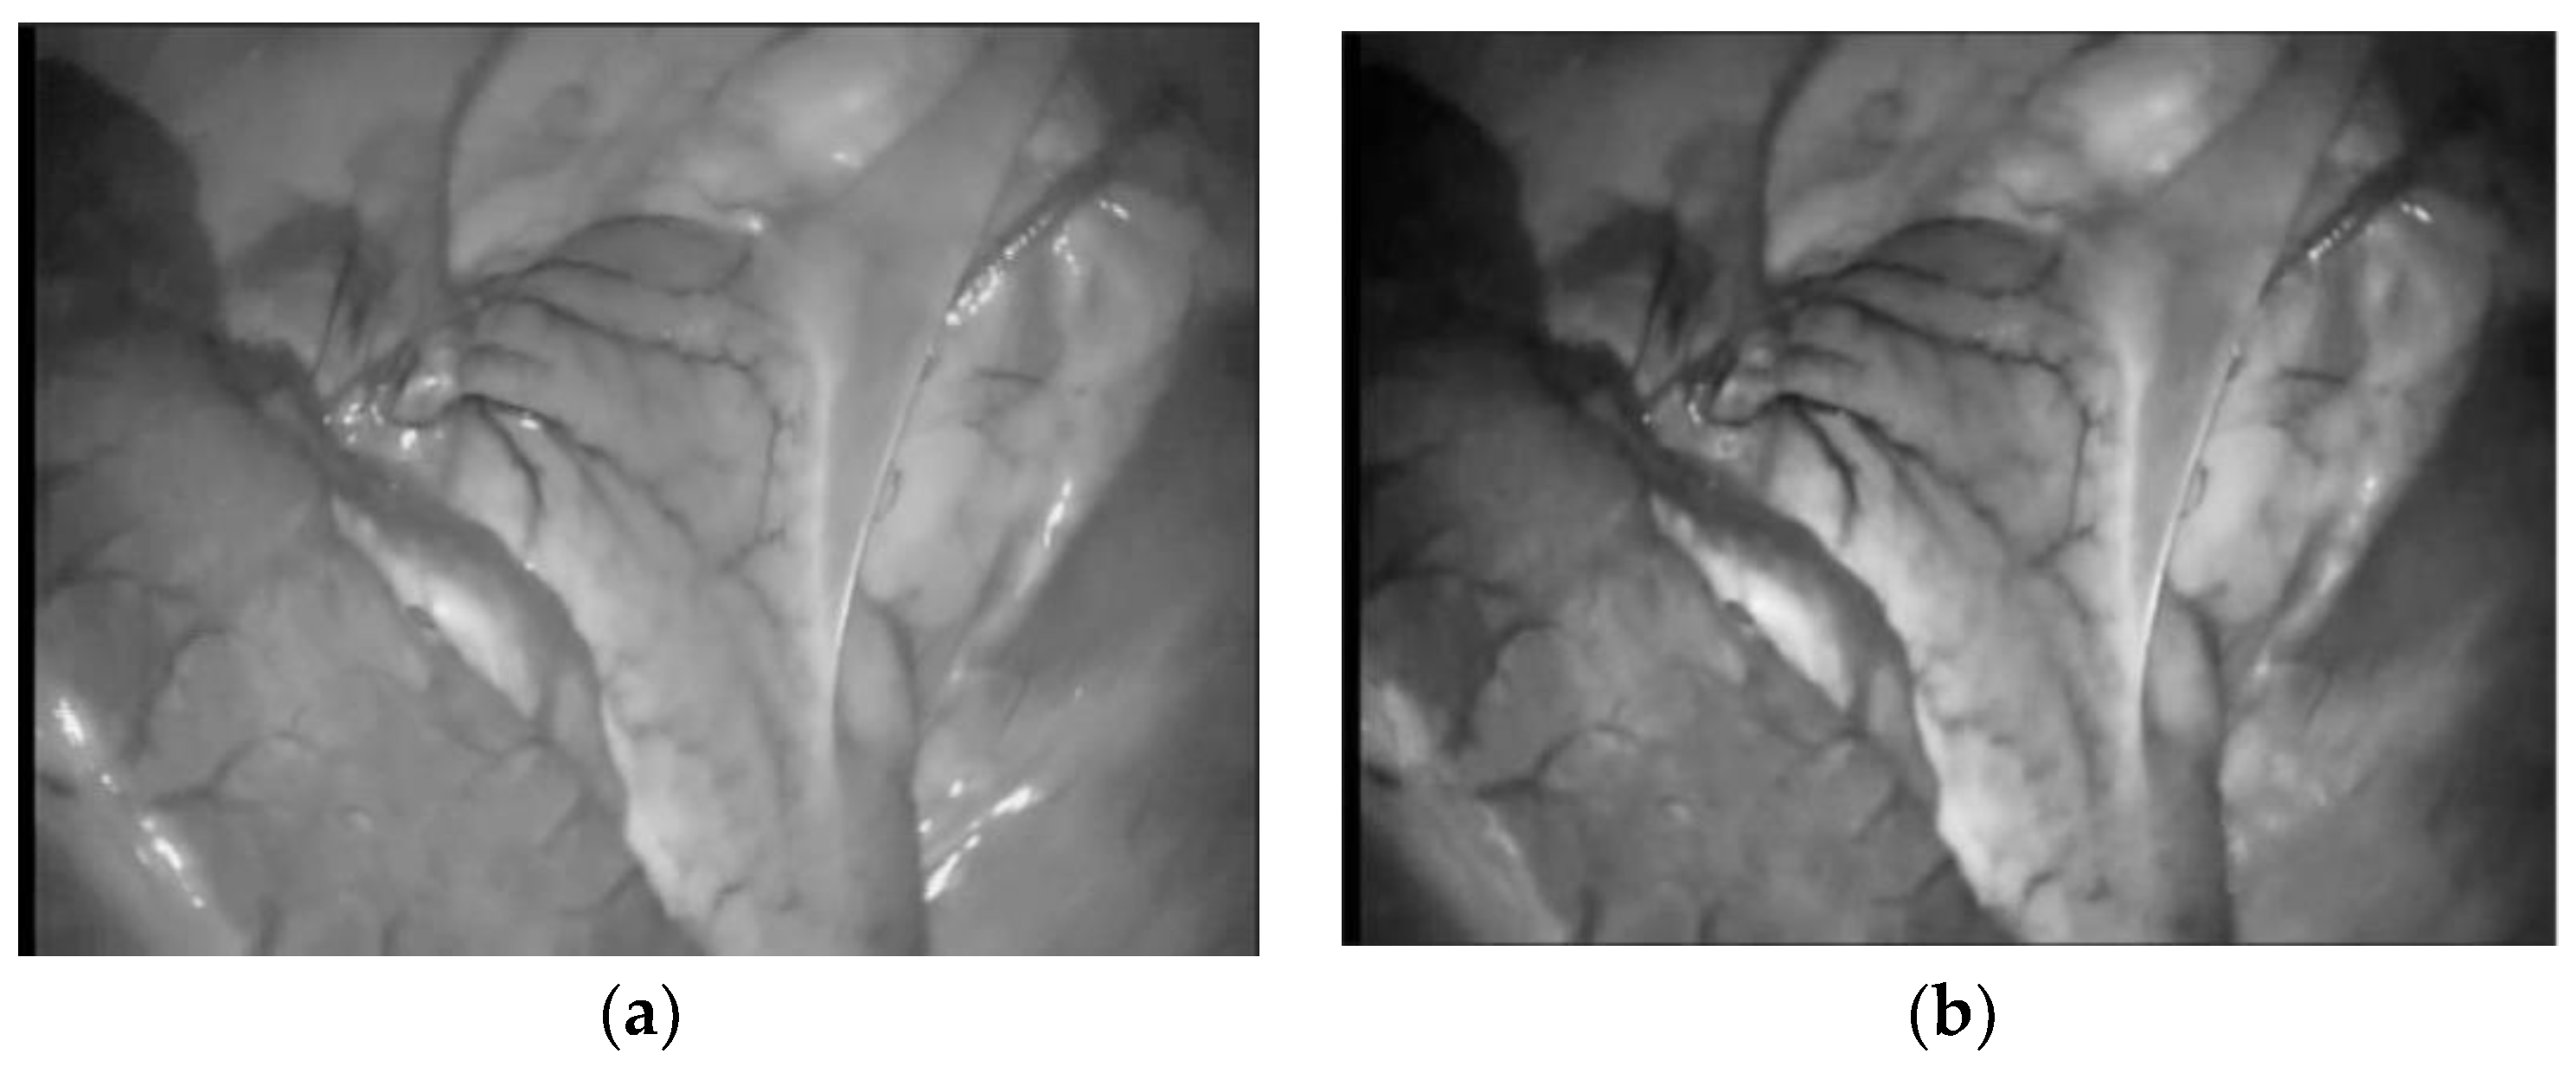

The preprocessing experiment is carried out in the human abdominal cavity image in Hamlyn medical image database, as shown in Figure 3. It can be seen that after preprocessing, the specular reflection area in the abdominal image is reduced, the contrast between the blood vessel and the background is enhanced, and the image texture is clearer.

Figure 3. Image pre-processing results. (a) The normal image; (b) The pre-processed images.

Symmetry 14 00185 g003